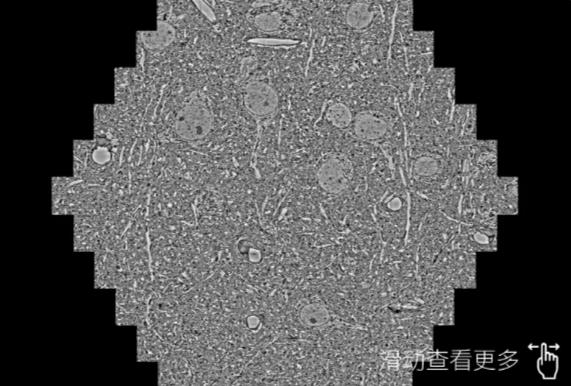

鼠脑切片。左图使用毕节蔡司毕节扫描电镜MultiSEM706对165μmx143pm面积区域成像,耗时仅需1.5秒。右图为鼠脑切片中30μm区域放大效果。样品由芝加哥大学B.Kasthuri提供。

使用蔡司高速毕节扫描电镜MultiSEM对1mm²人脑皮层组织进行高分辨成像,并对其中的各种细胞结构进行三维重构分析。左图展示了2x3mm²组织平面中锥体神经元的三维重构效果。右图显示了局部体积神经元三维重构。图像由哈佛大学chtman实验室提供,渲染图由D. Berger 制作。